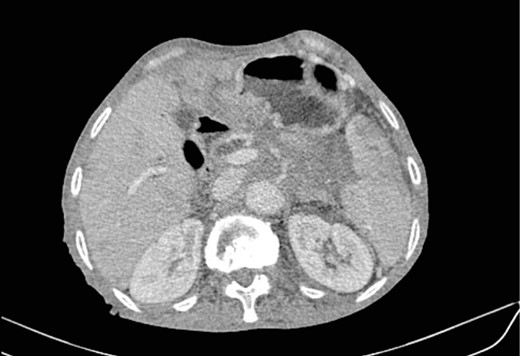

Mr. A. is a 65-year-old hypertensive patient presenting with acute epigastric pain associated with abdominal bloating. Biological settings showed amylasemia at 450 IU/L and lipasemia at 525 IU/L. Abdominal CT scan revealed heterogenous poorly defined mass in the pancreatic head with low enhancement (Figs 1 and 2). The CA 19–9 assay was 280 IU/L. Cephalic duodenopancreatectomy was performed. Histological examination of the operative specimen revealed a solid, trabecular, undifferentiated carcinomatous process (Fig. 3) expressing markers (CK(AE1-AE3) and p40) (Fig. 4), confirming the diagnosis of primary squamous cell carcinoma of the pancreas. The extension study showed no secondary localization.

Parenchymal atrophic changes and main pancreatic duct dilatation distal to the mass (blue arrow). Extra and intrahepatic bile ducts are dilated (red arrow).